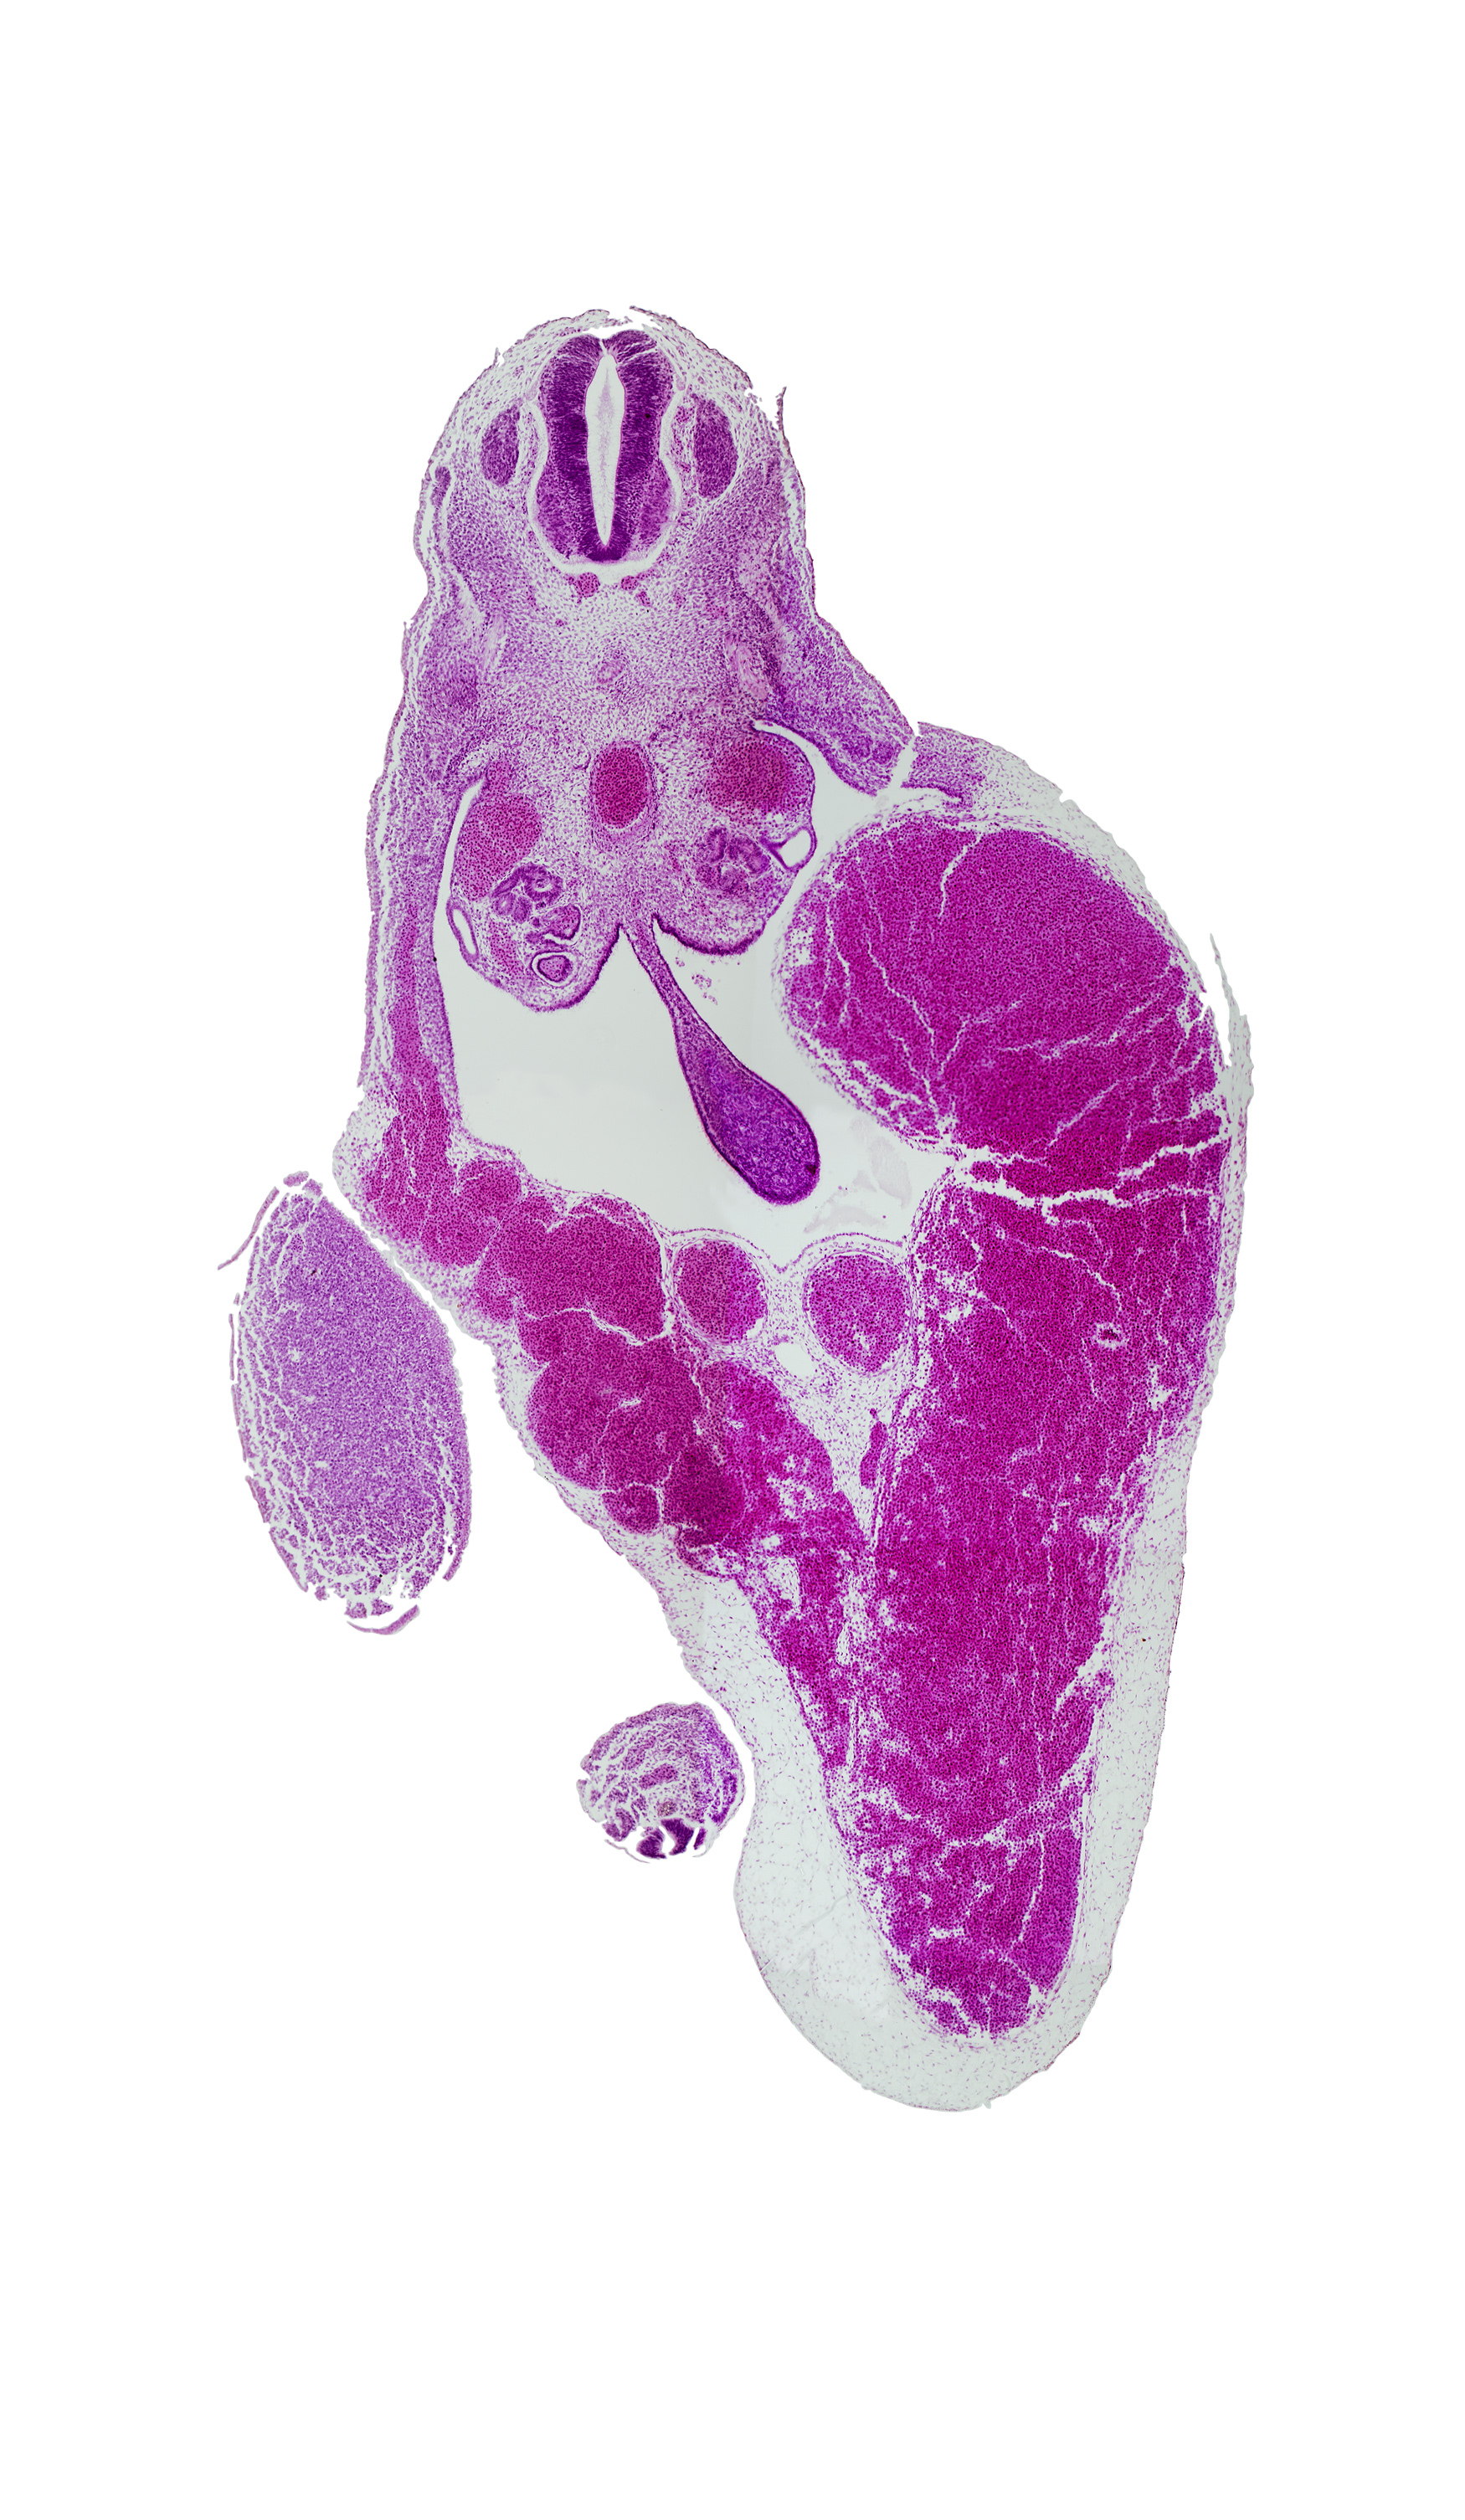

Carnegie Embryo #721 | Location: 22-01-05

Keywords: T-9 spinal ganglion, aorta, caudal eminence, common umbilical vein, dermatomyotome, dorsal mesentery, gonadal ridge, junction of umbilical veins, left umbilical vein (congested), mesonephric duct, midgut, peritoneal cavity, rib primordium, right umbilical vein, umbilical cord

Source: The Virtual Human Embryo.